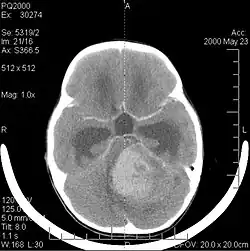

A tomografia computadorizada (TC) e a ressonância magnética (RM) podem detectar efetivamente uma neoplasia no cérebro. A RM é mais sensível que a TC para identificar lesões, mas contraindicações para pacientes com marcapasso cardíaco, próteses incompatíveis, clipes metálicos e outros. A TC continua sendo o método de escolha para detectar calcificações dentro de lesões ou erosões ósseas da calota craniana ou da base. A utilização de agentes de contraste, que são iodados no caso da TC e paramagnéticos ( gadolínio ) no caso da RM, permite a aquisição de informações sobre a vascularização e integridade da barreira hematoencefálica, uma melhor definição do tumor tumoral comparado ao edema circundante e à geração de hipóteses sobre o grau de malignidade . O exame radiológico também permite avaliar os efeitos mecânicos e consequentes alterações nas estruturas cerebrais decorrentes do tumor, como hidrocefalia e hérnias, cujos efeitos podem ser fatais. Finalmente, na preparação para a cirurgia, esse diagnóstico pode ser usado para determinar a localização da lesão ou a infiltração do tumor em áreas vitais do cérebro. Para isso, a RM é mais eficiente que a TC, pois pode fornecer imagens tridimensionais.

A tomografia computadorizada do cérebro normalmente mostra uma massa de tecido que pode ser realçada por qualquer contraste. Na TC, os gliomas de baixo grau geralmente parecem isodensos ao parênquima normal e, portanto, podem não apresentar realce pelo contraste. Da mesma forma, lesões na fossa posterior do crânio são difíceis de identificar na TC. Consequentemente, os resultados dessa tomografia isoladamente nem sempre são suficientes para fins diagnósticos. Em casos duvidosos, o uso da ressonância magnética mais sensível é essencial.

As metástases cerebrais são as neoplasias intracranianas mais comuns em adultos, sendo dez vezes mais comuns que os tumores cerebrais primários. Eles pisam em 20 até 40 por cento dos adultos com câncer e estão associados principalmente ao câncer de pulmão e mama e melanoma . Essas lesões resultam da disseminação de células cancerígenas pela corrente sanguínea e ocorrem mais comumente na junção da substância cinzenta e branca, onde a seção transversal dos vasos sanguíneos se altera, aprisionando embolias de células tumorais . 80 por cento das lesões ocorrem nos hemisférios cerebrais, 15 por cento no cerebelo e 5 por cento no tronco cerebral. Cerca de 80 por cento dos pacientes têm história de câncer sistêmico e 70 por cento têm múltiplas metástases cerebrais.

Avanços significativos foram feitos recentemente no diagnóstico e tratamento dessas lesões, resultando em melhora da sobrevida e controle dos sintomas. O início dos sinais e sintomas é semelhante ao de outras lesões maciças no cérebro. O método diagnóstico de escolha é a ressonância magnética com meio de contraste.